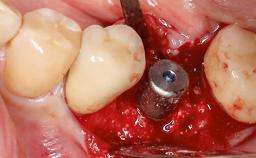

Replacement of a Failing Upper Right Central Incisor, Ridge Preservation and Late Placement of a NC Bone Level Implant

A 30-year-old patient presented at our clinic with a chief complaint of pain in her endodontically treated right maxillary central incisor (tooth 11) with a post-and-core and a fixed single crown. She had a very high lip line, a medium to thin soft-tissue phenotype, and a medium scalloped gingival contour. She also had high esthetic expectations because of her young age and beautiful smile. However, her expectations were realistic and she understood the risks of the treatment. At the initial clinical examination there was a slight mobility of tooth 11; no fistula was observed. The patient also had a single crown on the adjacent tooth 21. Both restorations were old and esthetically deficient. A digital periapical radiograph showed a very small periapical radiolucency, a thick intraradicular post, and no separation between root fragments.